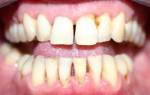

На фотографии продемонстрирована тяжелая форма периодонтита с кровоточащими деснами.

На фотографии показана тяжелая форма периодонтита с серьезной рецессией костной ткани и десен.